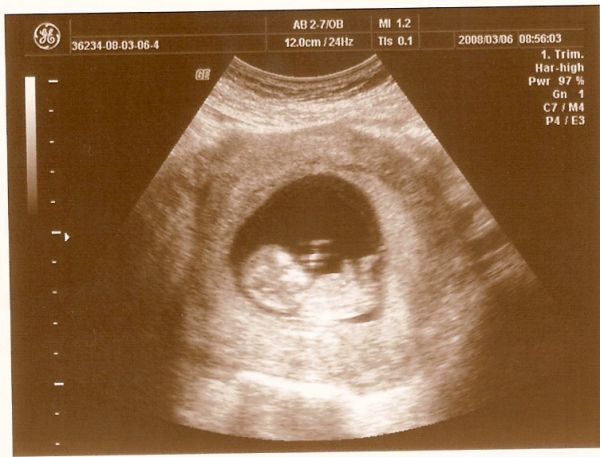

Roni kérdezted sima uh. volt.A doki magyarázta, hogy miből tudja ilyen biztosra megmondani ilyen korán.Hülyeséget nem akarok írni, de valami kis dudort vagy valamit nézett :roll: :oops: , hogy ha az merőleges a gerincvonalra akkor kislány, ha párhuzamos akkor kisfiú.Bocs, de annyira figyeltem és akkora volt az izgalom, hogy ennyi maradt meg.Valami japán kutatásokat is említett, na, szóval ő biztosan tudja mit miért mondott.Én hiszek és bízom benne.A lányom a maradék 5%-ban bízik, persze mondta, hogy örül, de sok olyat hallott már, hogy végig mást mondtak.....

és akkor a fotók,

+ egy kép a takarítás közben készült babalakról. Kép Kép